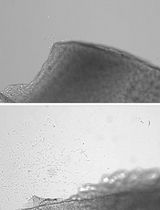

- Under an inverted microscope, healthy islets are picked with a P200 sterile pipette tip. Healthy islets have smooth borders in the absence of dark centers (Figure 1). Visual examination of the islets can provide basic information regarding health. Hand-picked healthy islets are then transferred into a new Petri dish containing 3 ml of fresh RPMI 10% FBS.

Figure 1. Images of pancreatic islets. Islets isolated before hand-picking (A). Purified islets after hand-picking (B). Scale bars represent 150 µm.